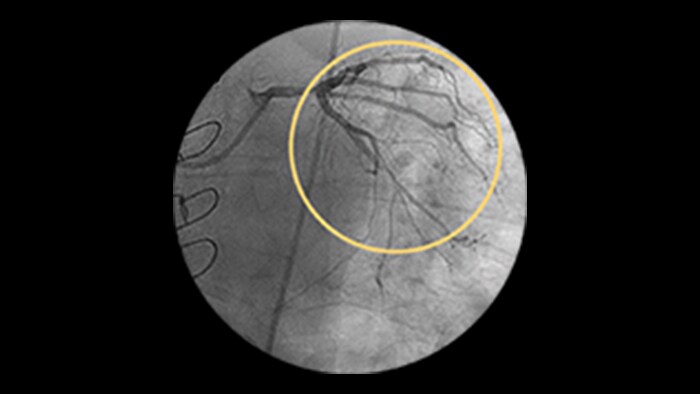

Incidence increases with age, yet older patients are less likely to have PCI attempted.1 Furthermore, 18% of PCIs have a CTO, but less than 5% are being treated.2